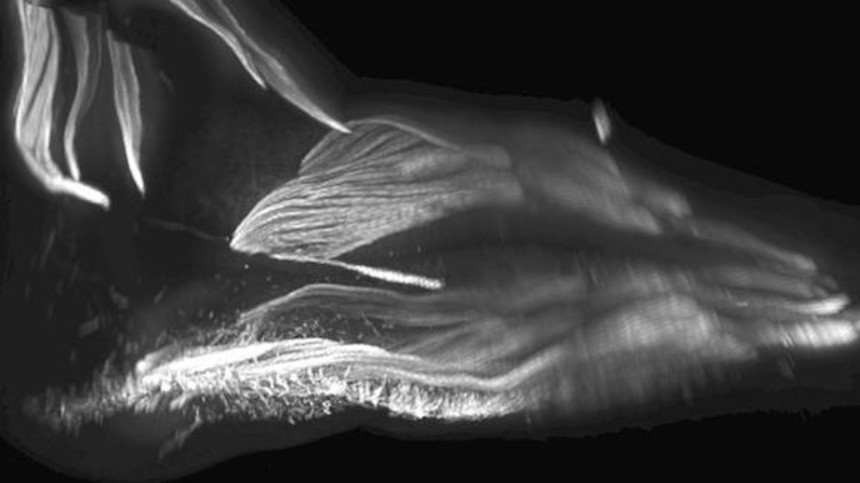

この画像を大きなサイズで見る赤ちゃんの足の筋肉

image credit:RUI DIOGO、NATALIA SIOMAVA AND YORICK GOTTON